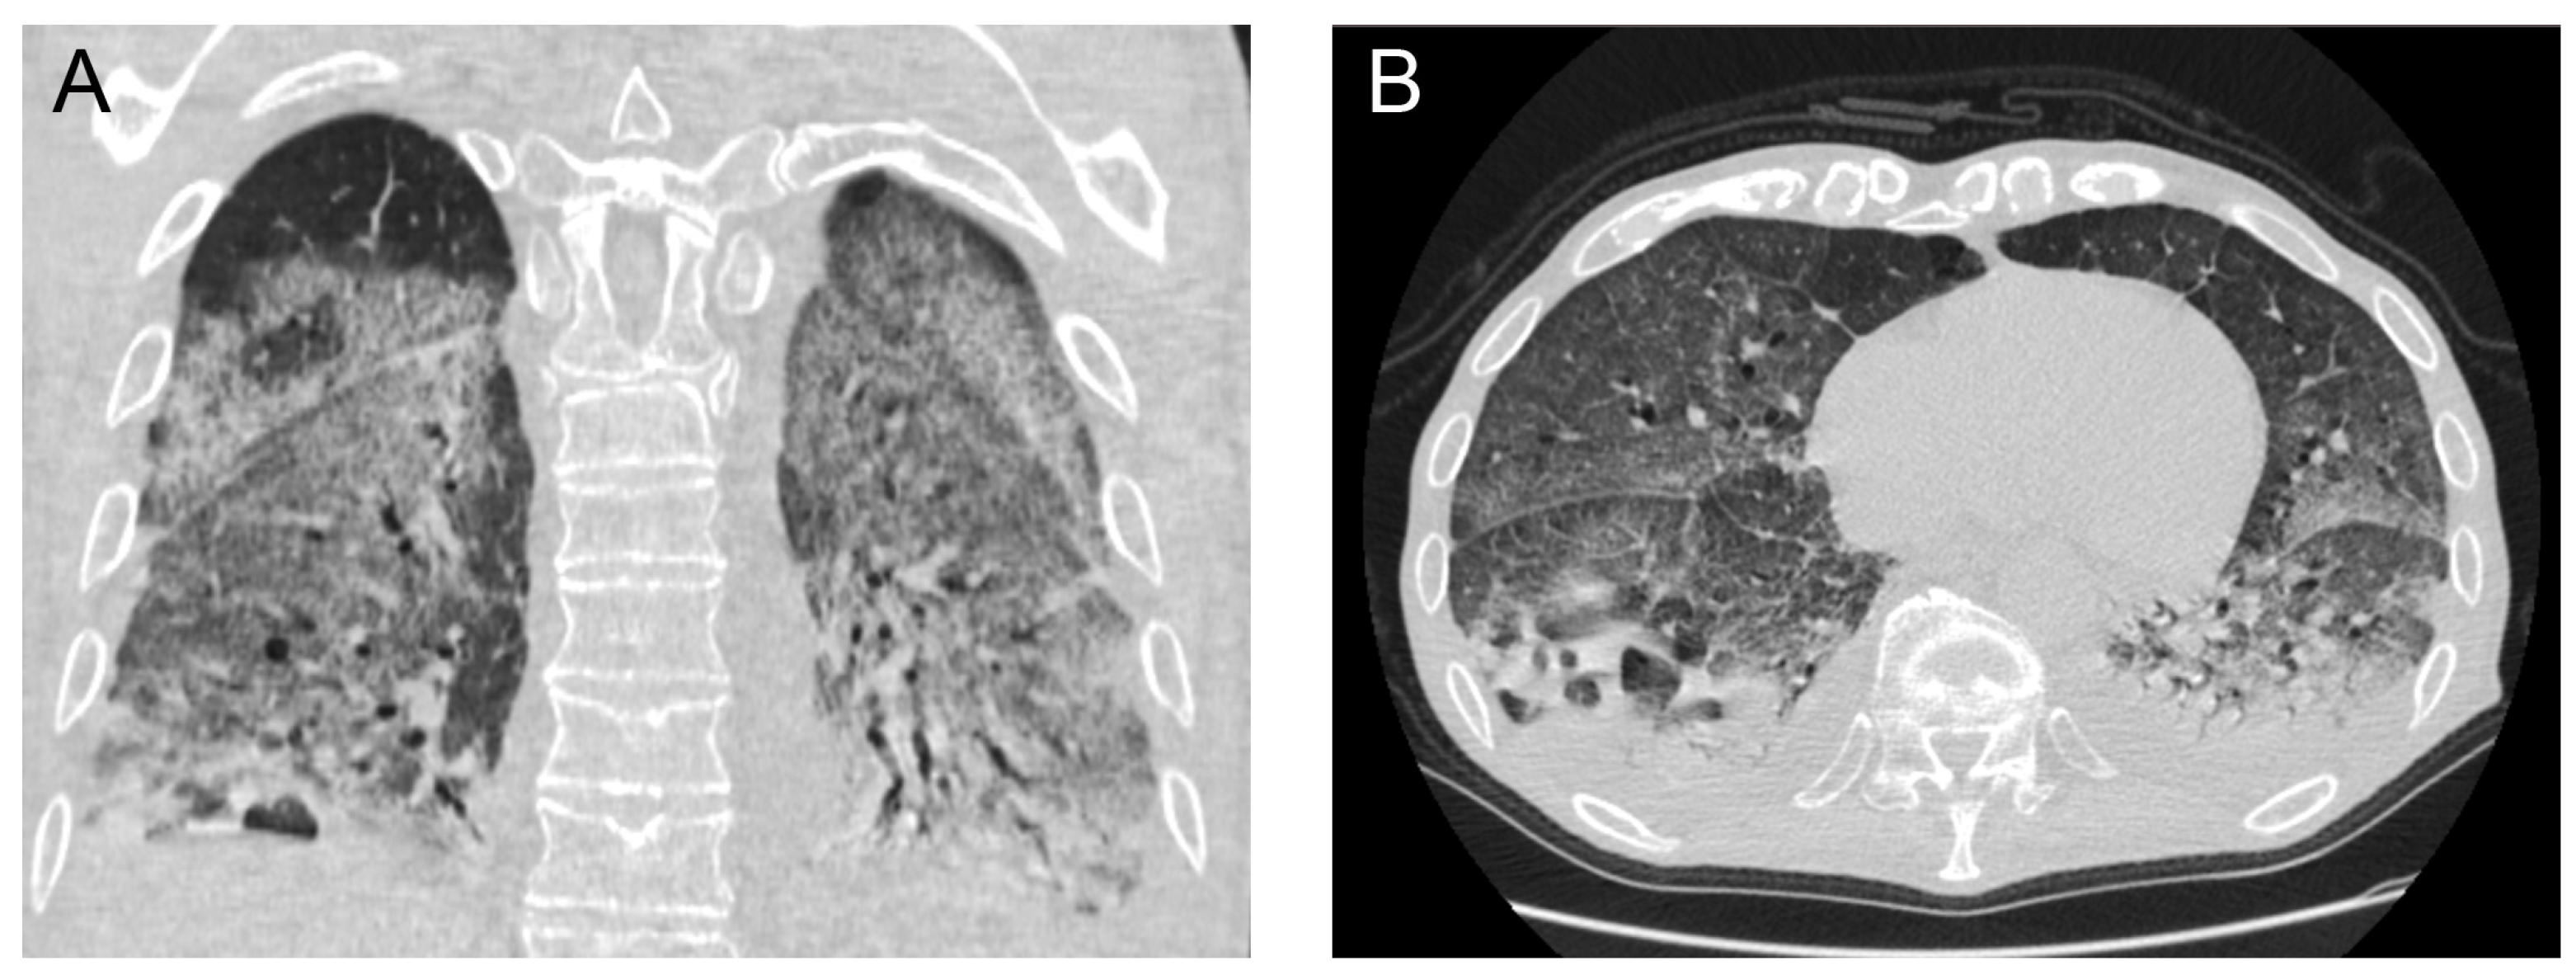

Laboratory investigations showed normal lymphocyte count with neutrophilia (89%) and severe lymphopenia (4.9%), increased C reactive protein (CRP) at 10.3 mg/L and normal procalcitonin (PCT) at 0.82 µg/dL. The rest of his laboratory values were within the normal range. His chest X-ray on admission presented with extensive consolidation and infiltrates mainly in the lower lung fields with blunting of the costo-diaphragmatic angles. His admission chest computed tomography (CT) scan demonstrated extensive ground glass infiltrates and diffuse consolidation bilaterally with a focus on the right lower lobe (Figure 1).

Figure 1.

Initial (on admission) chest computed tomography scan in coronal (A) and axial (B) views demonstrating extensive bilateral areas of consolidation and ground glass infiltrates, with lung cavitation mainly on the posterior segment of the right lower lobe.

The patient’s initial chest CT demonstrated significant areas of diffuse consolidation and patchy ground glass opacification. These are findings which have previously been associated and described with COVID-19 viral pneumonia [7]. In addition, in hindsight there seemed to be a focus of atelectasis and consolidation in the right lower lobe which could represent the precursor of the lung abscess.